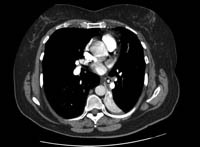

Chest CT of a patient with amiodarone pulmonary toxicity, showing asymmetric opacities with a peripheral distribution

From the personal collection of Dr A. Pataka and Professor P. Argyropoulou, Aristotle University, Thessaloniki, Greece